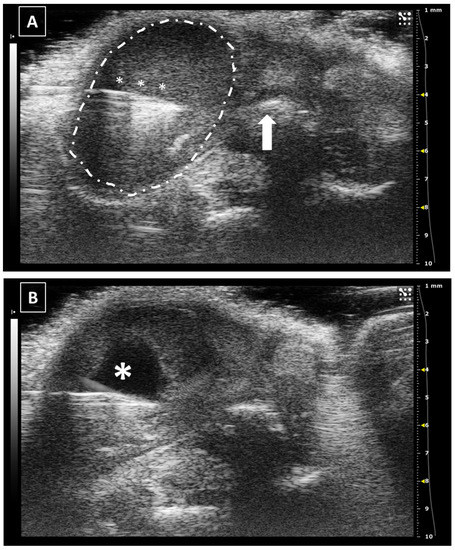

The uterine injection using ultrasonography is one of the most difficult techniques, especially when the organ is in repose (not gravid). The structure is long, thin, and mobile, and the uterine wall is hard. All these characteristics make the intrauterine injection a challenging process. The less mobile part of the uterus is the neck which stays anatomically fixed in place. In this part of the organ, the injection could be feasible. On the other hand, for injecting the uterine horns they should be externally exposed with a surgical opening of the abdomen. For intrauterine injections, the previously published works never went over 30 microliters [37,38,39,40]. Like in the other injections, we should keep the needle in place for some seconds before removing the needle. Figure 8 shows a representative image of a uterine injection.

Figure 8. Intrauterine injection. (A) The uterus is punched but no fluid is administered. The needle is marked with white asterisks. The uterus is surrounded by a dashed line. The urinary bladder is marked with a big white asterisk. (B) Same structure after administration. The fluid collection is marked with a dotted line. Images obtained at 40 MHz frequency.